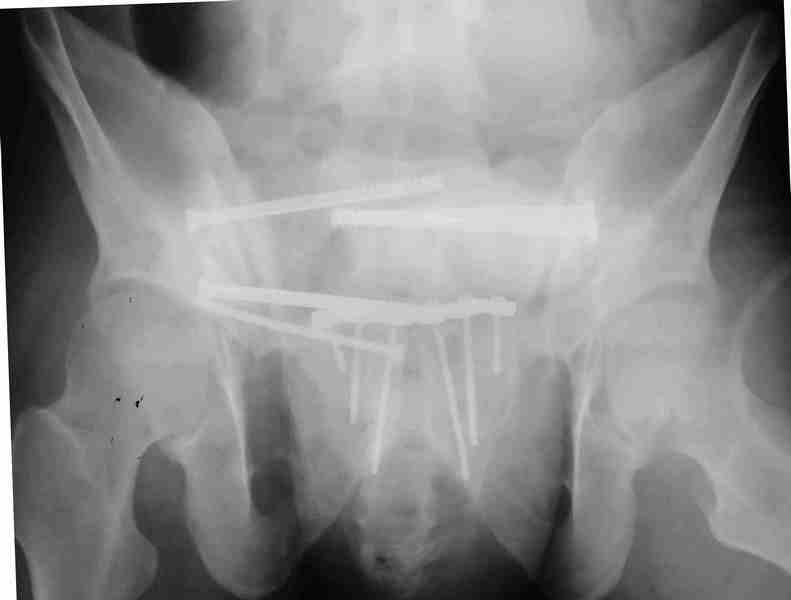

Коллеги, как и когда вы бы разрешили нагрузку в такой ситуации.

Молодой парень, без соматики. Сейчас чуть больше 2-х нед после операции,

швы сняты, мочится сам. Был тяжелый, после операции дней 10 пытался

выполнить лежа поперечный шпагат (успешно, так и лежал большей частью,

может быть из-за обширной гематомы промежности). Репозиция не

идеальная, но фиксация довольно надежная, за 2 нед ничего не

разъехалось". Сейчас пришел в ум. Когда, по-вашему, можно дать нагрузку,

и на какую ногу, или на обе? Или вообще подскажете

программу реабилитации.

PS Заранее извиняюсь за качество снимков, до не делали (body scan),

если не видно - то - полные разрывы КПС с двух сторон. после КТ

сломался. Неврологии вроде бы нет.